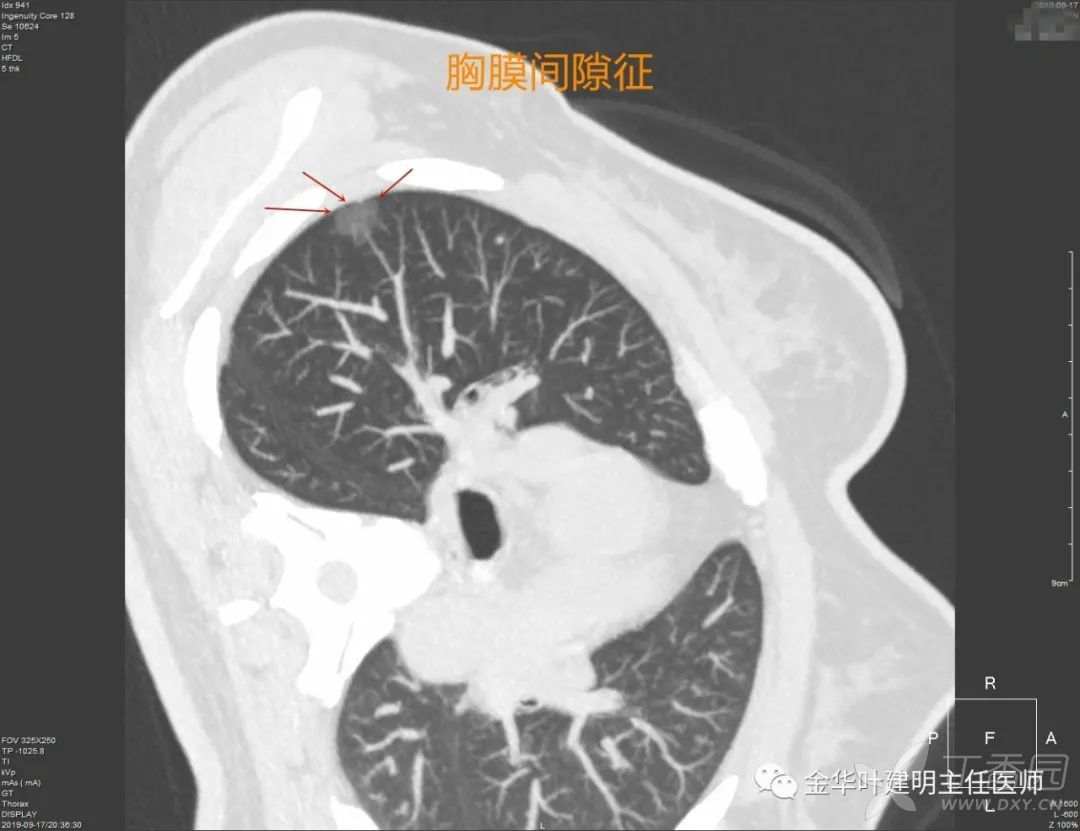

胸膜间隙征

胸膜间隙征:这个名称也是我取的,正规来说,应该没有这种叫法。要表达的意思是,病灶与胸膜挨的非常近,但却有极小的间隙存在,说明:

1、病灶非炎症性,炎症的话,有渗出或水肿,往往离这么近的话,间隙消失了;

2、说明病灶收缩力弱,一般是磨玻璃结节或实性的话,像周围型鳞癌或小细胞癌等收缩力弱的肿瘤。